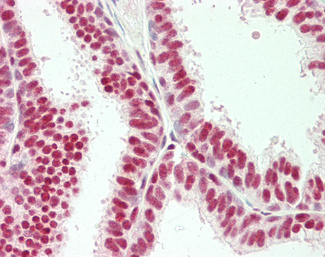

Estrogen Receptor / ESR1

Anti-ER Alpha / Estrogen Receptor antibody IHC staining of human breast. Immunohistochemistry of formalin-fixed, paraffin-embedded tissue after heat-induced antigen retrieval. Antibody LS-B10527 dilution 1:100.